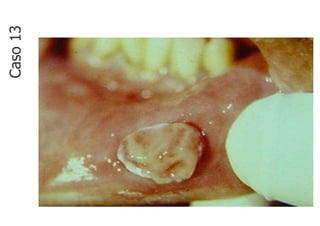

Caso

13

• Lesão fundamental: Nódulo pediculado (com

superfície ulcerada)

• Localização: Mucosa gengival inferior do lado

esquerdor

• Quantidade: única

• Tamanho (mm): 2,0 cm x 1,5 cm

• Borda: bem delimitada

• Cor: esbranquiçada

• Base: séssil

• Aspecto superficial: lobulada

• Em mucosa labial inferior nota-se nódulo vegetante

pediculado, esbranquiçado, único, bem delimitado,

com base de implantação na mucosa pediculada,

superfície ulcerada e que mede aprox. 2,0 cm x 1,5

cm de diâmetro.

CASO 13 - Descrição